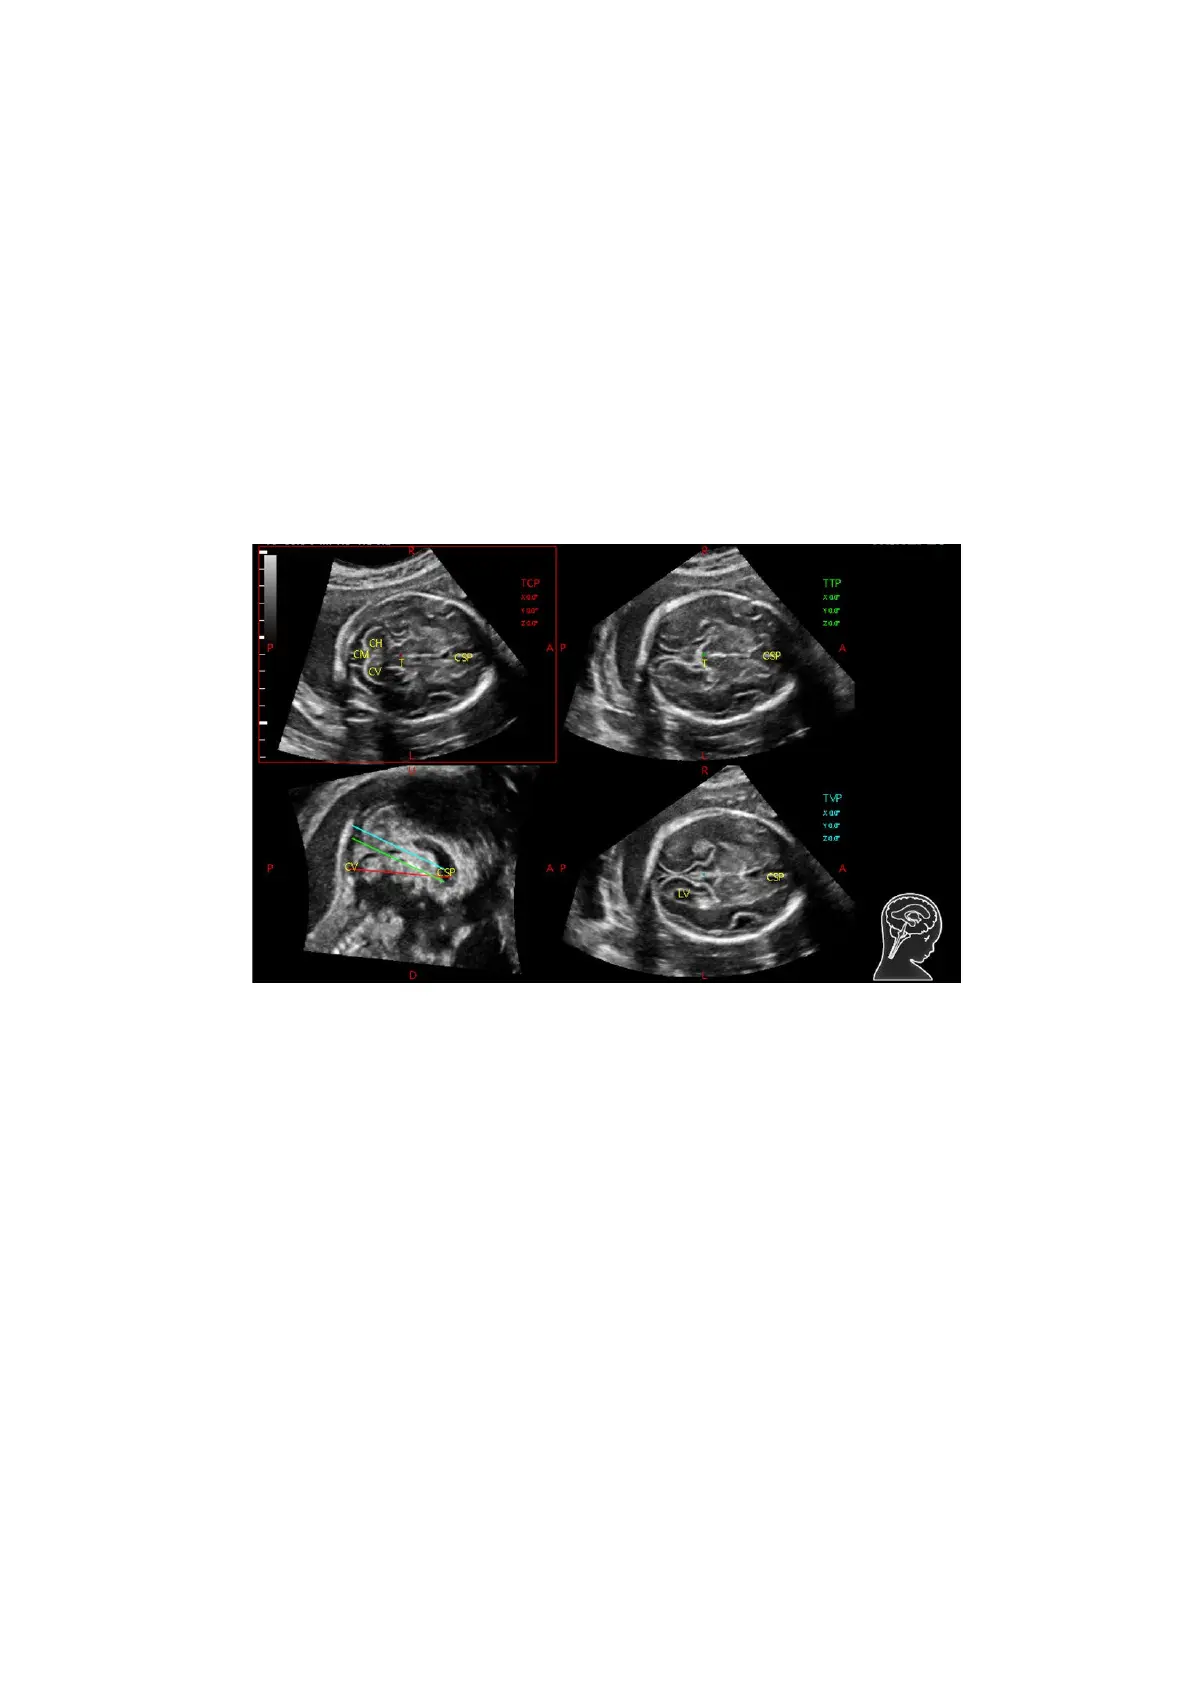

1. Acquire 3D data. Tap [S-Planes CNS] to enter the automatic detection of the mode.

2. Click [Auto Comment]. The comments appear on the image automatically.

Each of them is:

The orientation comments describe the location of the plane, referring to A (anterior), P

(posterior), L (Left), R (right), U (up), D (down).

Organ comments describe the position of the organ, referring to CSP (cavum septum

pellucidum), T (thalamus), CH (cerebellar hemisphere), CV (cerebellar vermis), CM (cisterna

magna), LV (lateral ventricles).